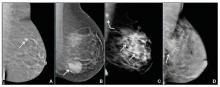

We’re all familiar with the adage that a picture is worth a thousand words. While the medical support personnel in your office are likely quite familiar with imaging reports and the terminology used in describing dense breasts, they may be quite unfamiliar with what a fatty versus dense breast actually looks like on a mammogram, and how cancer may display in each. Illustrated examples, as seen here, are useful for reference.

In the fatty breast (A), a small cancer (arrow) is seen easily. In a breast categorized as scattered fibroglandular density (B), a large cancer is easily seen (arrow) in the relatively fatty portion of the breast, though a small cancer could have been hidden in areas with normal glandular tissue.

In a breast categorized as heterogeneously dense (C), a 4-cm (about 1.5-inch) cancer (arrows) is hidden by the dense breast tissue. This cancer also has spread to a lymph node under the arm (curved arrow).

In an extremely dense breast (D), a cancer is seen because part of it is located in the back of the breast where there is a small amount of dark fat making it easier to see (arrow and triangle marker indicating lump). If this cancer had been located near the nipple and completely surrounded by white (dense) tissue, it probably would not have been seen on mammography.

Image: Courtesy of Dr. Regina Hooley and DenseBreast-info.org